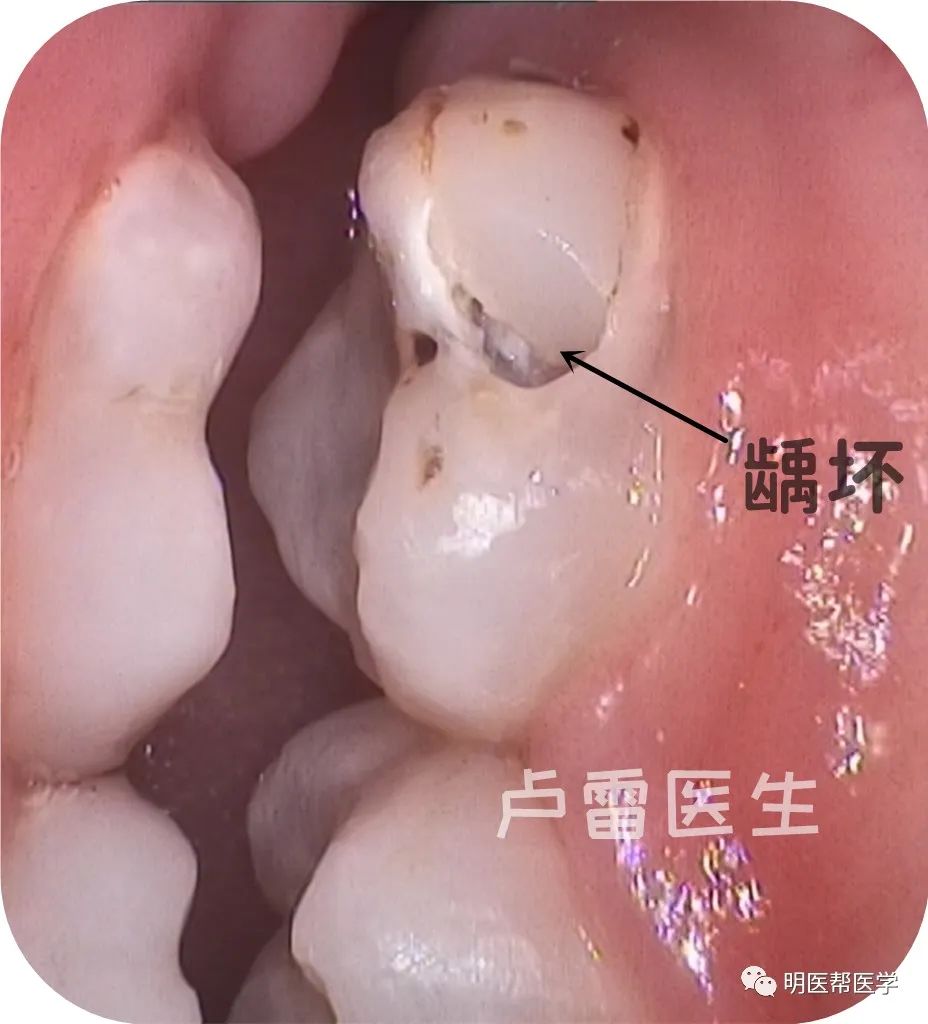

补牙后崩裂龋坏颊侧面观

去除原充填材料后发现有洞底有龋坏,洞深。